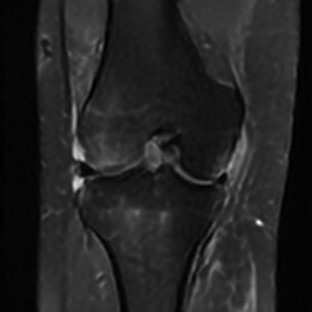

Limited by imaging systems, the reconstruction of Magnetic Resonance Imaging (MRI) images from partial measurement is essential to medical imaging research. Benefiting from the diverse and complementary information of multi-contrast MR images in different imaging modalities, multi-contrast Super-Resolution (SR) reconstruction is promising to yield SR images with higher quality. In the medical scenario, to fully visualize the lesion, radiologists are accustomed to zooming the MR images at arbitrary scales rather than using a fixed scale, as used by most MRI SR methods. In addition, existing multi-contrast MRI SR methods often require a fixed resolution for the reference image, which makes acquiring reference images difficult and imposes limitations on arbitrary scale SR tasks. To address these issues, we proposed an implicit neural representations based dual-arbitrary multi-contrast MRI super-resolution method, called Dual-ArbNet. First, we decouple the resolution of the target and reference images by a feature encoder, enabling the network to input target and reference images at arbitrary scales. Then, an implicit fusion decoder fuses the multi-contrast features and uses an Implicit Decoding Function~(IDF) to obtain the final MRI SR results. Furthermore, we introduce a curriculum learning strategy to train our network, which improves the generalization and performance of our Dual-ArbNet. Extensive experiments in two public MRI datasets demonstrate that our method outperforms state-of-the-art approaches under different scale factors and has great potential in clinical practice.